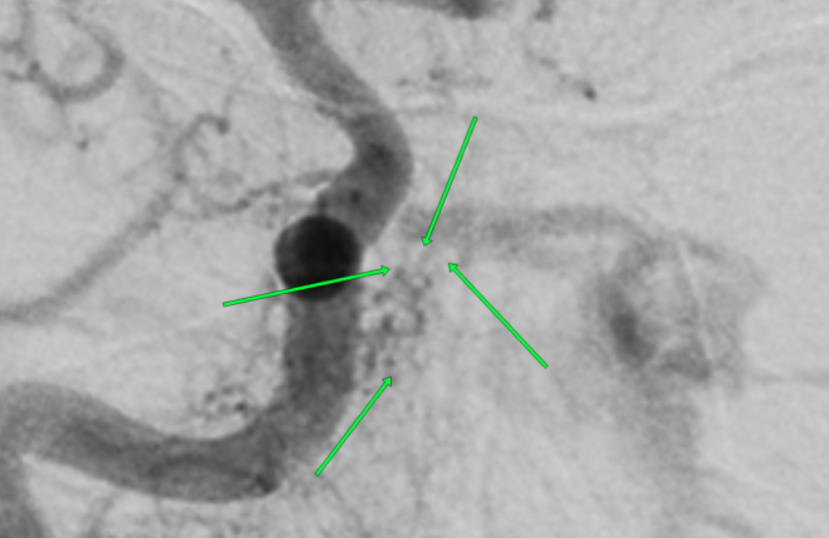

右侧颈总动脉正位造影,海绵窦区硬脑膜动静脉瘘,间窦显影。左侧海绵窦显影,向左侧眼上静脉,左侧岩下窦引流,左侧颈外动脉引流

不能排除此处瘘口

瘘口?

右侧颈外动脉造影,海绵窦区瘘